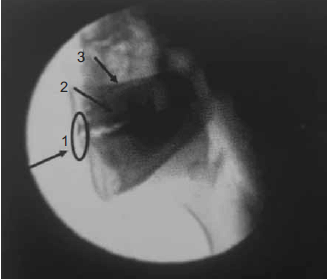

Para análise da VFD, é necessário o conhecimento da anatomia e fisiologia em um exame normal para que possa identificar possíveis alterações. A figura a seguir enumera três regiões anatômicas necessárias de serem visualizadas durante o exame.

(Magalhães e Magnoni. Disfagia Orofaringea. 2022. p. 78)

Assinale a alternativa que apresenta, correta e respectivamente, as regiões anatômicas enumeradas na figura.